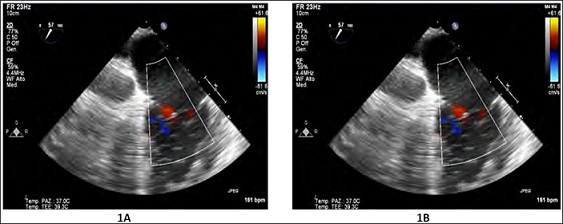

Supplementary Movie 1: Two-dimensional color Doppler Transthoracic Echocardiography (TTE) apical four-chambers views. The moderate mitral regurgitation at baseline (A) became mild at three months postoperatively (B).